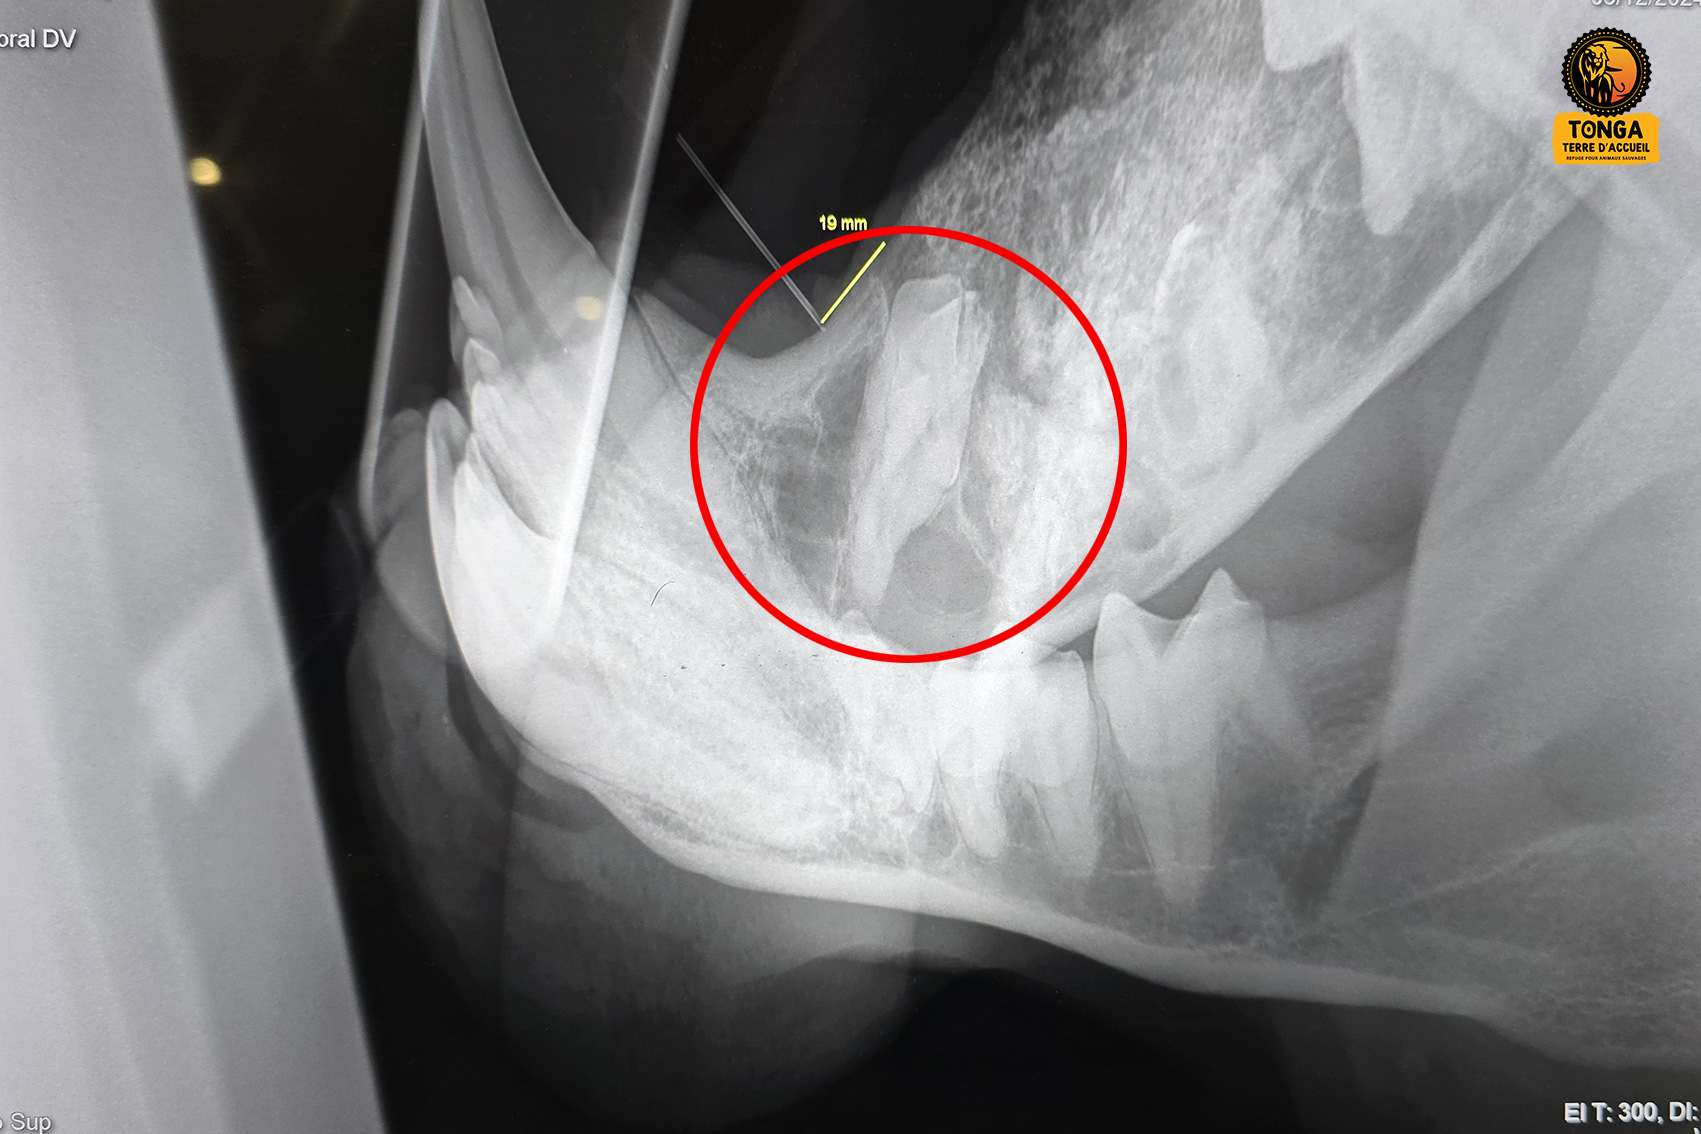

En raison d'une anomalie génétique, les dents définitives de Yembé ne sont jamais sorties sur sa mâchoire inférieure droite. Cette rétention a provoqué des kystes qui fragilisent cette partie de la mâchoire. Le risque de fracture spontanée étant très important, Yembé ne peut pas être nourri avec de la viande contenant des os. L'opérer est donc devenu une nécessité, afin de lui offrir la possibilité de manger normalement, et écarter ce risque permanent de fracture de la mâchoire.

Un scanner a été réalisé au mois de juin 2024, qui a permis de mieux comprendre la pathologie dentaire de Yembé, et localiser les dents qui n'ont jamais poussé. Deux interventions chirurgicales sont nécessaires pour extraire les deux dents restées coincées dans la mandibule, à tour de rôle, à quelques mois d'intervalle.